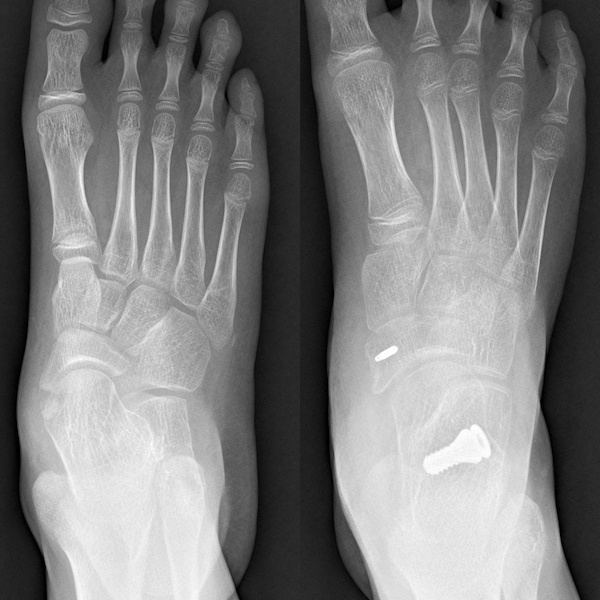

Flatfoot, as the name suggests, refers to the collapse of the arch of the foot. In fact, flatfoot is a multi-dimensional deformity, not only manifested as the collapse of the medial longitudinal arch but also including rearfoot valgus, and in severe cases, it may even cause ankle valgus. The collapse of the arch and rearfoot valgus are often accompanied by a pronation deformity of the forefoot.

Collapse of the Arch in Flatfoot

Rearfoot Valgus and Medial Prominence in Flatfoot

What is Subtalar Joint Bracing Surgery?

Subtalar joint bracing surgery is a surgical intervention measure for the further treatment of flatfoot that is unresponsive to conservative treatment. It is a minimally invasive treatment method that corrects the deformity of flatfoot by placing a "screw" between the sinus tarsi, talus, and calcaneus, known as a subtalar joint stabilization screw.